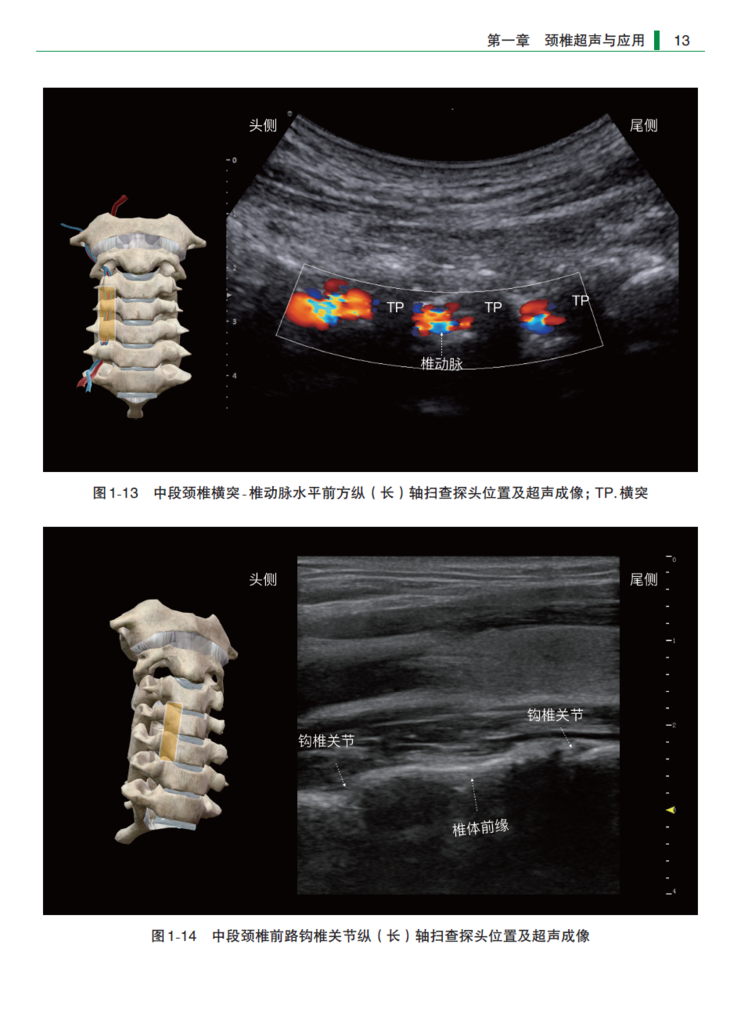

本书依据颈椎、胸椎、腰椎及骶尾椎的顺序,对区域阻滞与疼痛相关治疗领域中常用的脊椎超声扫查切面进行了系统而详细的解析。本书共分4章,共75个超声扫查切面。概述了各个节段脊椎的解剖及超声成像特点,分别按照纵轴扫查和横轴扫查的方法详细介绍了获得每个切面的扫查步骤,同时配以精美的超声解剖图像及探头位置示意图加以说明,并以表格的形式汇总各个超声扫查切面的应用,便于临床医生实际操作过程中快速查阅。此外,本书还在同一部位并列对比了专用于脊椎扫查的手持超声与传统超声的扫查图像,为读者提供了全面的参考信息。本书可作为有一定超声基础的麻醉科、疼痛科及介入科等临床医生快速掌握超声引导下脊柱相关操作的参考用书。